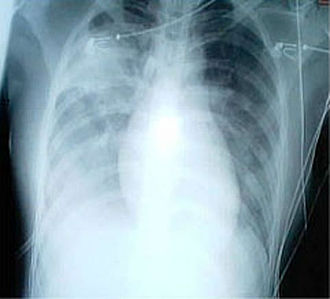

- atipična upala oba plućna krila, rendgenska snimka pluća na početku bolesti pokazuje infiltrate kod gotovo 80 % bolesnika

Vjerojatni slučaj SARS-a ima, uz gore navedeno i rengenski nalaz atipične pneumonije ili akutno zatajanje pluća. Sam snimak ne potvrđuje SARS, ali abnormalni infiltrati u plućima se uzimaju kao dokaz. Početni snimak pluća može biti normalan.